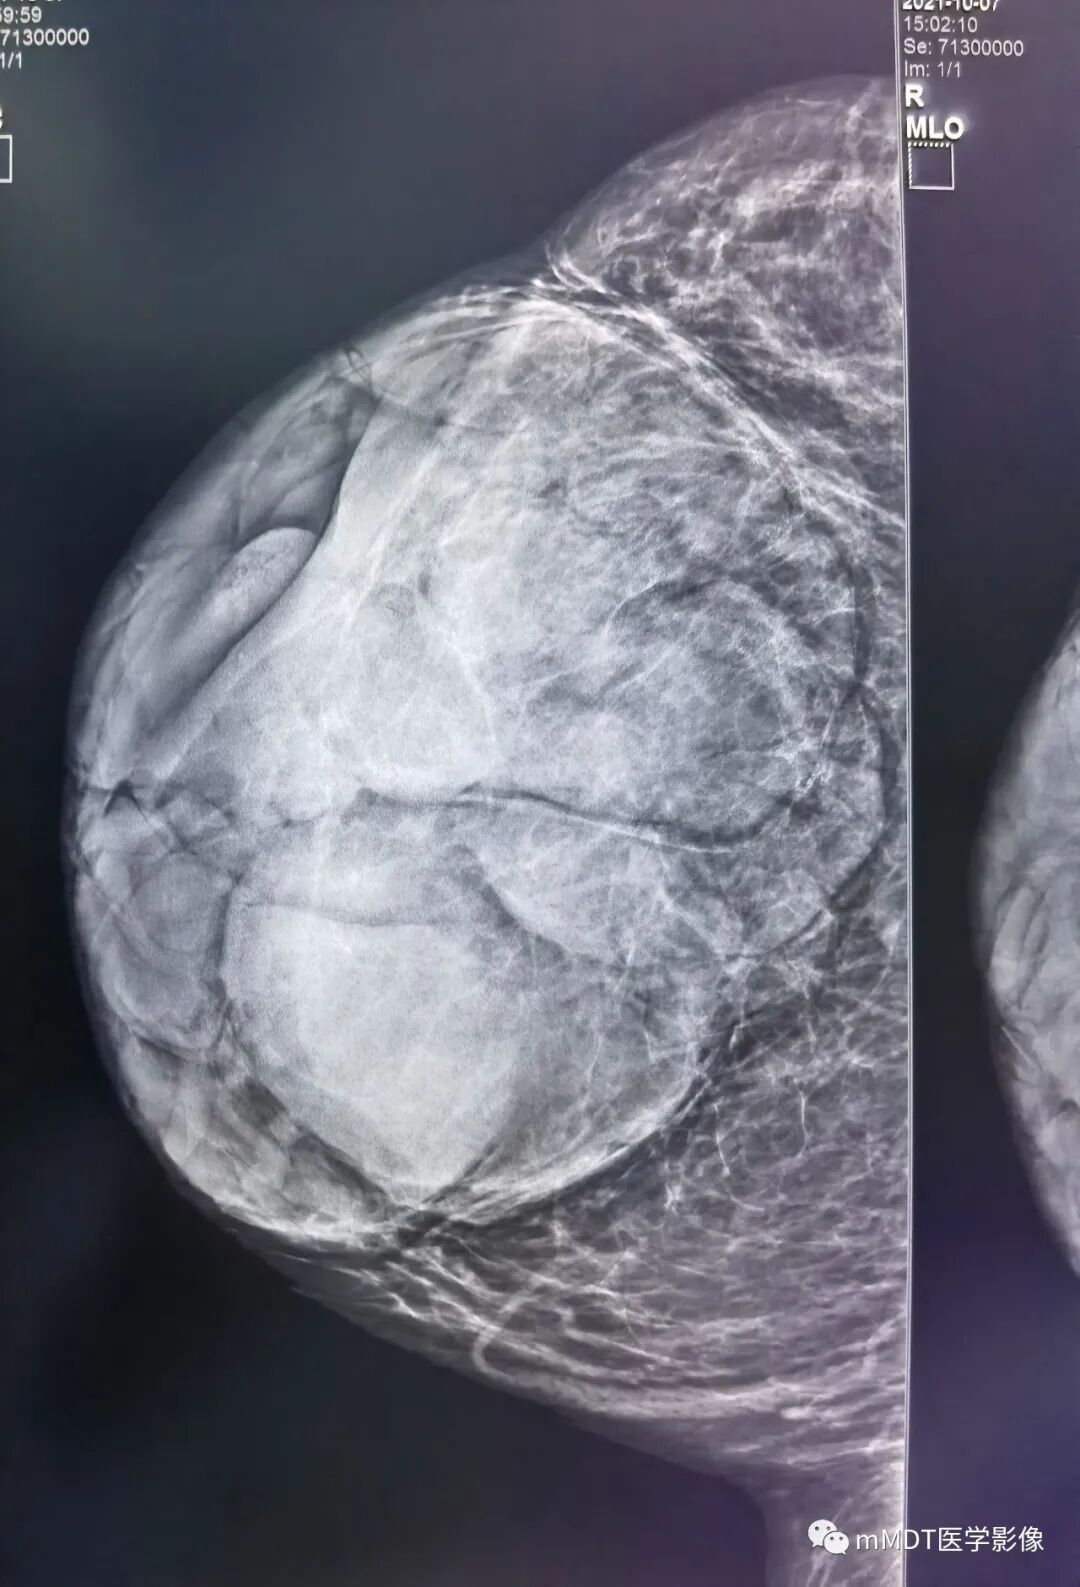

右乳外上象限约9点-10点钟方向后1/3带距胸壁cm可见一不规则肿块,边缘清晰,其内可见斑点钙化灶,大小约,右侧腋窝未见肿大淋巴结,虽然形态学看着良性,但是逐渐增大,考虑4a,建议穿刺活检或核磁检查。

乳腺腺体呈c类;右乳外上象限后带不规则等密度肿块,大小约--,边界清晰,内见点状钙化影;考虑4A类。MR:右乳外上象限后带距胸壁cm可见一不规则肿块,大小约--,边缘清晰,T1呈稍低信号,T2压脂呈高信号,内见低信号分隔影,DWI呈高信号,ADC值1.7,动态增强早期快速强化,TIC曲线呈流入型,考虑纤维腺瘤,BI-RADS 3类。

晨读:中老年女性,病程较长,钼靶右乳外上象限约9-10点钟方向,后1/3带可见一不规则肿块,分叶,边缘清晰,其内可见小斑点状钙化灶,乳腺腺体内见散在斑点状钙化灶,腋窝未见肿大淋巴结,结合年龄和逐渐增大病史,考虑4a,建议穿刺活检或核磁检查。B超低回声?边界清晰

双乳腺体类型为ACR C型,右乳外上象限约10点钟方向位于乳房后1/3带腺体边缘可见一不规则肿块,边缘清晰,其内可见粗细不等颗粒样钙化灶,右侧腋窝未见实性肿大淋巴结,BI-RADS分类:4A,纤维上皮性肿瘤可能(结合年龄,近期增大的病史。分叶状肿块常见纤维腺瘤或者叶状肿瘤,合并粗大钙化者,纤维腺瘤机会大一些)

双测乳腺体类型为ACR C型,右乳外上象限约11点钟方向位于乳房后1/3带可见一不规则椭圆形肿块,边缘清晰,其内可见粗细不等颗粒样钙化灶,右侧腋窝未见实性肿大淋巴结,BI-RADS分类:3纤维腺瘤可能,

右侧乳腺C型,右侧乳腺外上象限10-11点方向键分叶状肿块高密度肿块,边缘清晰,其内见少许点状钙化,乳头未见回缩,右侧腋窝见结节状密度增高影;超声病灶边缘稍显欠光滑,分叶;MRI:T1WI脂肪抑制等信号,T2WI脂肪抑制等高混杂信号,DWI高信号,ADC值约1.7,增强:背景强化a,为病灶早期明显强化,呈流入型。余未见明显异常。

双侧乳腺ACR呈B型,右侧乳腺外上象限后1/3带可见不规则等密度肿块,边缘清晰,其内可见几枚点状钙化,腋窝未见肿大淋巴结影。